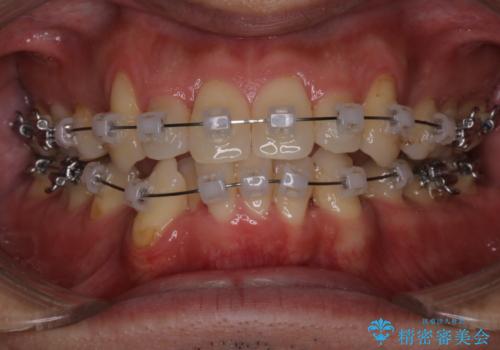

- 治療計画

叢生量が大きいため、上下顎両側4番を抜歯しました。矯正治療による歯肉退縮の著しい悪化もなく、主訴であるガタつきも改善できました。